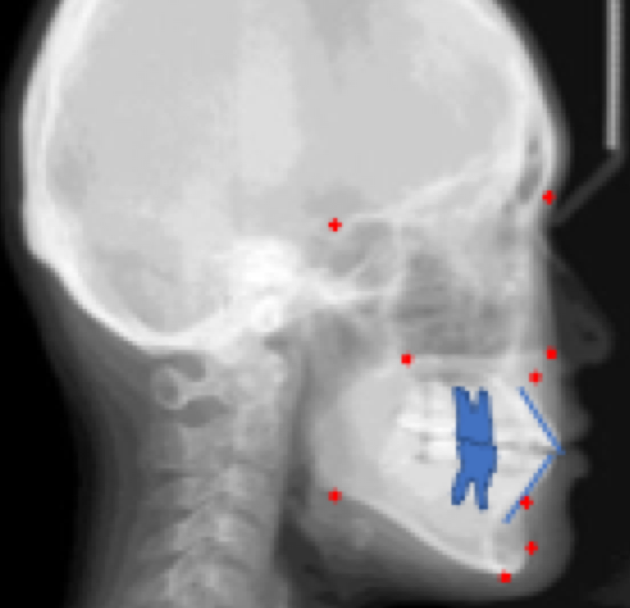

Name all landmarks

top back - Sella (S)

top front - Nasion (Na)

middle back - PNS

middle front - ANS

middle below - Point A

low back - Gonion (Go)

low bottom - Menton (Me)

low front - Pogonion (Pog)

low front - Point B

blue - dental landmarks U1, L1, U6, L6